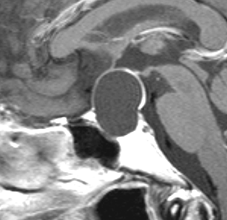

この画像はプロラクチンが上昇 (51ng/ml) して生理不順になった20代女性のものです。プロラクチン産生腫瘍には見えません。左の画像では嚢疱が2つ見られます。右の画像では,上の嚢疱に液面 fluid-fluid levelが見られて,腫瘍内の出血があったようにもみえます。手術後の病理診断は両方共にラトケのう胞でした。プロラクチン値は正常に戻りました。

でも手術中の所見では,上方のものは黄色肉芽腫のようで,のう胞内用液は頭蓋咽頭腫のように廃液用のドロッとした暗緑褐色のもので,さらにキラキラ光るコレステリンの結晶がたくさん出てきました。下の嚢疱は黄褐色の通常のラトケのう胞の内容液でした。両方ともに下垂体の正常腺組織とは区別がつかない繊維化した壁があって,危うく下垂体機能損傷を生じるところでしたが難を避けました。

このような腫瘍では下垂体機能障害を招いてしまうことが多いので,嚢疱を破るだけにとどめて壁となっている組織を積極的に摘出しない方がいいでしょう。下垂体腺腫でもなく頭蓋咽頭腫でもなく,炎症性組織あるいは肉芽腫様に見えたら切除を中断することが肝要です。